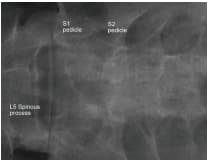

Investigations included MRI of the Lumbosacral spine which showed a large Tavlov Cyst at S1 on the right and S2 on the left. There was no bony erosion.

There was a large cyst at S1 and S2 communicating with the main dural sac via a narrow neck. The pressure in the cyst changes with filling of the cyst. Sacral nerves travel through the neck of the cyst to exist the sacral canal. As such, we decided on simple decompression of the S1 root and a laminectomy and not excision of the cyst which will require the sacrifice of sacral nerves passing through the neck and cyst.